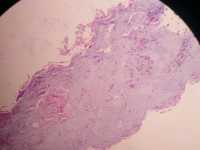

右手小指关节肿物,

性别

男

年龄

61

临床诊断

无

一般病史

标本名称

肿物

大体所见

多快小组织0、6*0、5cm